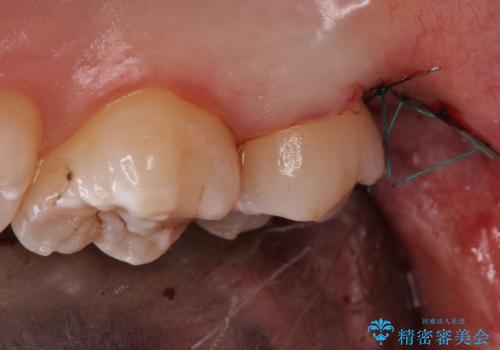

- 親知らず抜歯をご希望で来院されましたが、手前の歯が歯ぐきに覆われていたため抜歯と同時に歯ぐきの除去を行います。

今回は親知らずの抜歯と同時に周りの歯茎の除去を行いました。